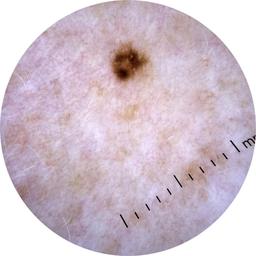

ISIC_6713563

2165 x 2165

age_approx 60

anatom_site_1 Upper extremity

diagnosis_1 Benign

diagnosis_confirm_type single image expert consensus

image_type dermoscopic